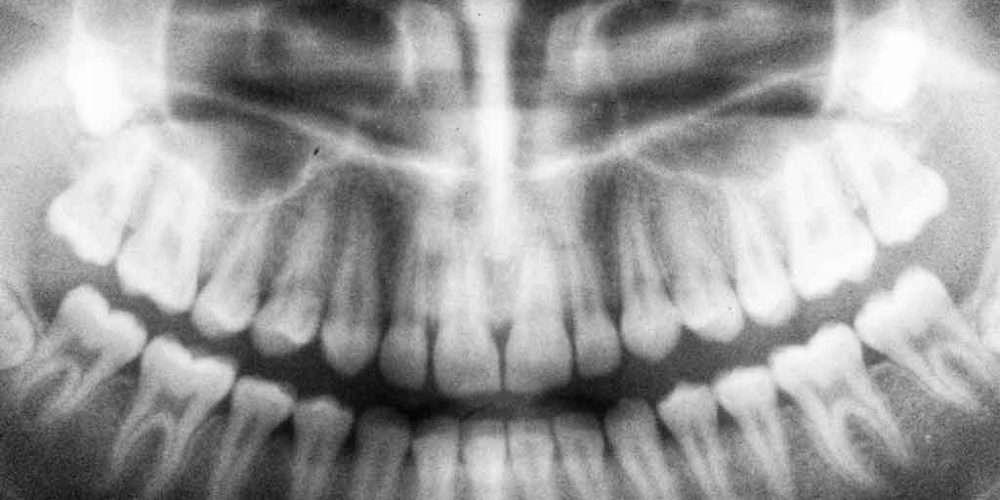

This is why dental clinics in Costa Rica—those working with international patients—invest in modern digital x-ray equipment. With digital x-rays, the view is much clearer, so diagnosis and treatment are much more accurate.

“Good digital dental x-rays allow our dentists to obtain highly detailed and accurate views of the teeth and jaws. These images are 3-D, so we can see a patient’s entire dental structure from any angle.”